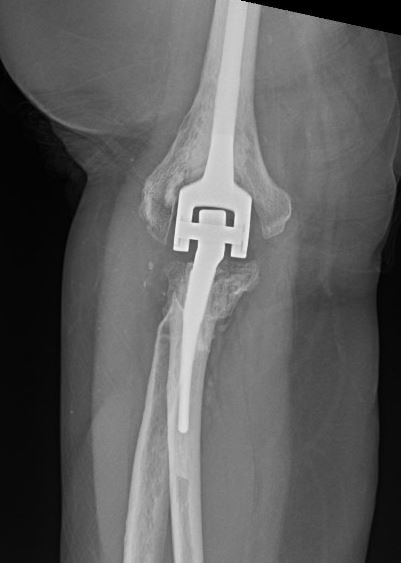

A 69-year-old male presents to the clinic for evaluation of right elbow pain with decreased range of motion. Fifteen months ago, the patient sustained a right elbow injury following a fall down the stairs and was treated with open reduction and internal fixation at an outside institution. Today, he reports continued pain and a gradual decrease in range of motion. On examination, significant crepitus is noted throughout elbow range of motion, with an arc of motion limited from 45 to 90 degrees. Pronation is limited to 40 degrees, while supination is limited to 30 degrees. Radiographs are obtained, as depicted in Figures A and B. Which of the following is true regarding the most appropriate treatment for this injury?

Figures A and B represent orthogonal views of a right elbow demonstrating post-traumatic osteoarthritis with heterotopic bone formation following olecranon ORIF and radial head replacement.